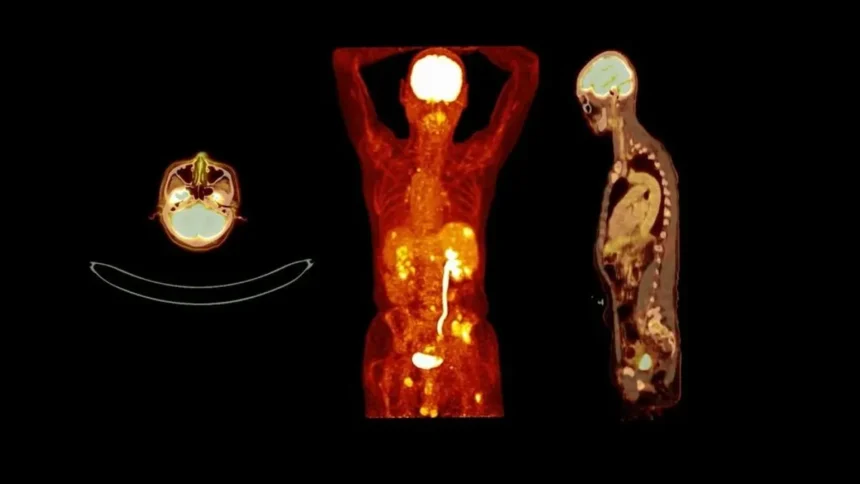

„A veserák különösen alattomosan fejlődik, mert hosszú ideig nem okoz észrevehető tüneteket. Amikor a betegek végre orvoshoz fordulnak, gyakran már késő stádiumban van a betegség,” magyarázza Dr. Kovács. A probléma súlyosságát jelzi, hogy az Országos Onkológiai Intézet 2025-ös jelentése szerint Magyarországon évente közel 2500 új vesedaganatos esetet diagnosztizálnak, és ez a szám folyamatosan növekszik.

Bár a veserák kezelése az elmúlt évtizedben sokat fejlődött, a gyógyulási esélyek még mindig szorosan összefüggnek a felfedezés időpontjával. Korai stádiumban a túlélési ráta meghaladja a 90 százalékot, míg késői felismerésnél ez 10 százalék alá csökkenhet. Ezért a szakemberek azt tanácsolják, ne habozzunk orvoshoz fordulni, ha bármilyen gyanús tünetet észlelünk, különösen ha a rizikócsoportba tartozunk.